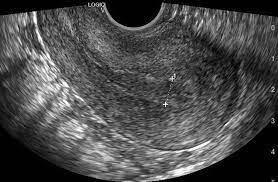

子宮內膜緻密度(endometrial compaction, EC)定義為從卵